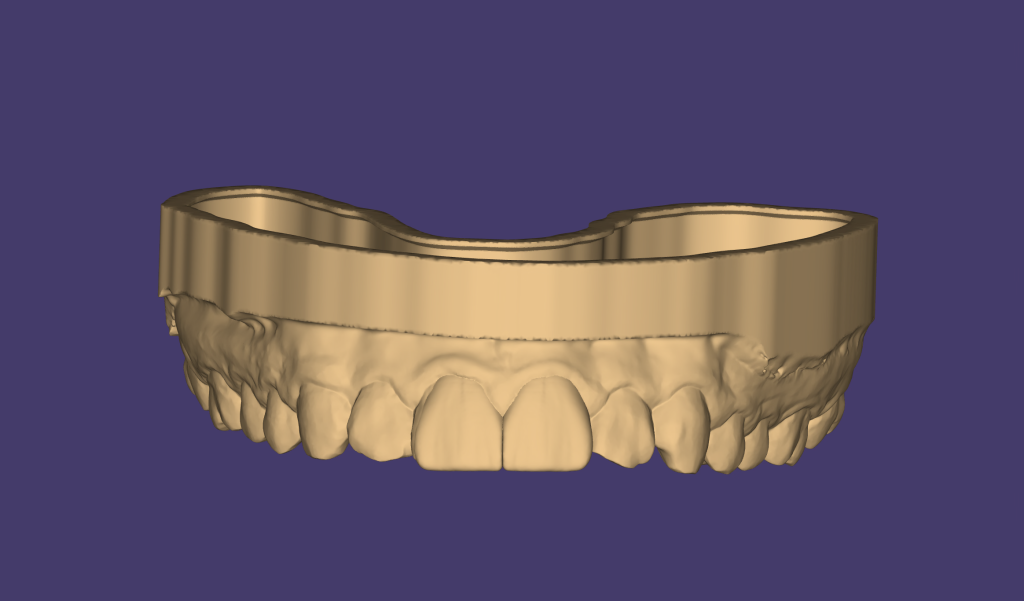

STEP 3 – Silica Index and Palatal Shell Fabrication

A 3D smile mock-up was designed and approved by the patient to define final tooth proportions and width-to-length ratios. A silicone putty index was fabricated from the mock-up to create a palatal shell. This shell provided a stable incisal edge position and guided functional envelope during reconstruction. (Fig.3)